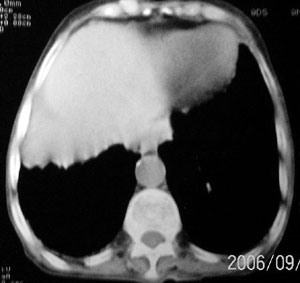

f 76 间断咳嗽 咳痰1年余 发热不明显 身体削瘦

征象:

1、右肺中叶近肺门区可见一空洞样病灶,内壁不规则,有与邻近支气管相通的征象,其外侧大片肺组织软组织状实变,余肺可见散在点、片絮状密度增高影,肺纹理可见明显增粗及串珠样改变;

2、纵隔气管前、隆突下、内乳组、心右前间隙以及右侧腋窝内均可见肿大的淋巴结节;

3、右侧胸膜增厚粘连,胸腔少量积液征像;

4、其它征像略。

诊断意见:

1、右侧中央型(空洞性)肺癌并双肺受累(包括转移、阻塞性炎症、癌性淋巴管炎);纵隔、右侧腋窝内淋巴结肿大、转移;右侧胸膜增厚粘连,胸腔少量积液;

2、双上肺陈旧性结核。

3、慢性支气管炎、肺气肿。